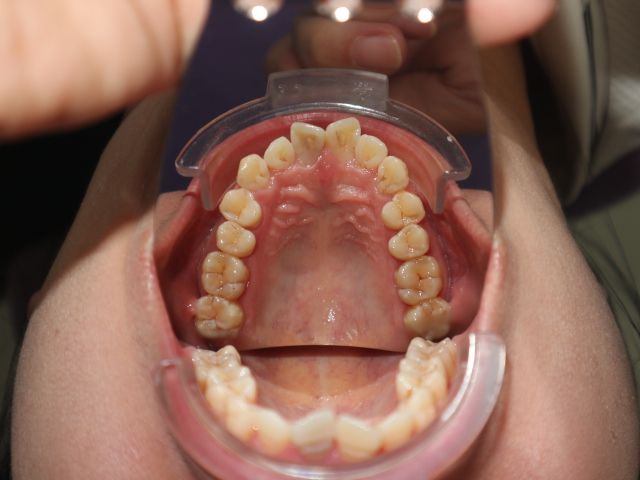

Nên niềng mắc cài hay invisalign cho tình trạng răng khấp khểnh vùng răng cửa, hô ở mức trung bình

Xin chào các bác sỹ Em đã đi tư vấn, các nha khoa đều đưa ra 2 lựa chọn mắc cài hoặc invisalign. Vậy em xin hỏi với trường hợp của em, phương pháp nào tối ưu, hiệu quả, tiết kiệm thời gian và an toàn hơn? Em cảm ơn.

Có thể khắc phục được tình trạng răng chen chúc xô lệch mà không cần nhổ răng không?

Tôi 23 tuổi và đang cân nhắc đến việc niềng răng để khắc phục tình trạng răng mọc khấp khểnh. Tôi đã đến gặp hai bác sĩ nha khoa thẩm mỹ và họ đều nói là cần phải nhổ răng nhưng tôi lại không muốn vậy. Hàm dưới của tôi gần như hoàn hảo nhưng tôi có tật nghiến răng vào ban đêm. Vậy tôi muốn hỏi là có thật sự cần phải nhổ răng hay không?